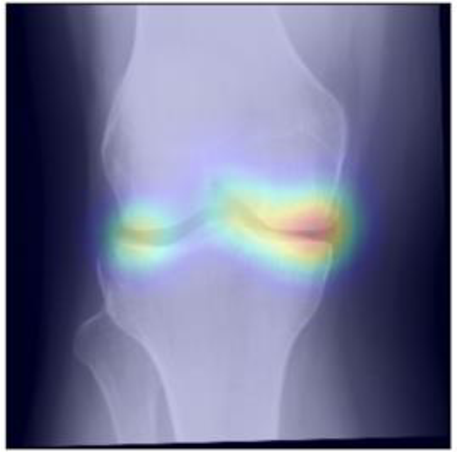

To gain insight into the basis of the CNN’s prediction, we used the GradCAM [24] approach and visualized the attention maps for the well-predicted knees. Examples of attention maps are presented in Figure 5. We observed that in various cases, the CNN paid attention to the compartment opposite to the one where degenerative change became visible during the follow-up visits. Additional examples of such attention maps are presented in Supplementary Figures 3, 4, 5 and 6.

Refer to caption

(a)

(b)

(c)

(d)

Figure 5: Examples of attention maps for progression cases and the corresponding visualization of progression derived using follow-up images from MOST datasets. Here, subplots (a) and (c) show the attention maps derived using a GradCAM approach. Subplots (b) and (d) show the joint-space areas from all the follow-up images (baseline to 84 months). Here, the subplot (b) corresponds to the attention map a) and the subplot (d) corresponds to the attention map (c).